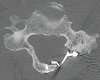

Cervical laminoplasty is a non-fusion, decompression procedure for cervical spondylotic myelopathy (CSM). It is most commonly indicated for patients with multilevel stenosis who have preserved sagittal alignment and minimal to no axial neck pain related to spondylosis. Expansion of the laminar arch can allow for direct and indirect decompression of the spinal canal. Relative contraindications include those patients with significant preoperative neck pain, kyphotic alignment and substantial instability. Potential advantages over laminectomy and fusion include avoiding fusion-related complications, and the preservation of motion. Important technical considerations include meticulous extensor muscle management, with special attention being given to preserving the soft tissue attachments to C2. In the properly selected patient, outcomes are comparable, and in some studies superior, to other operations for CSM.